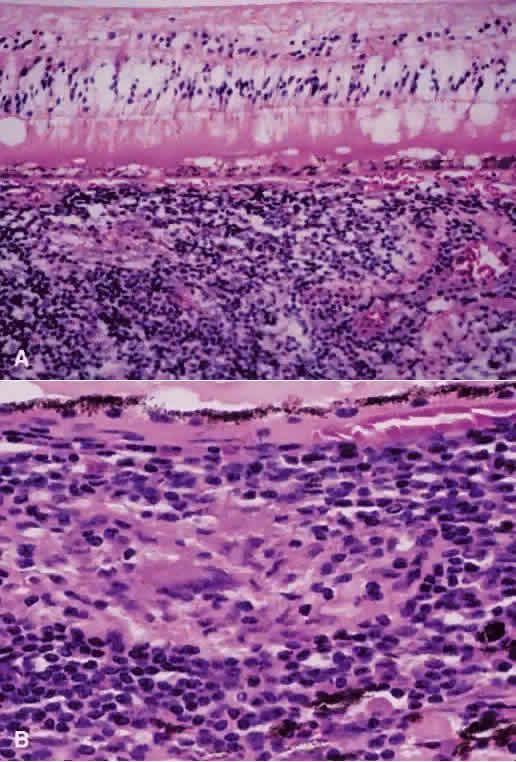

Early events in EAU include expression of adhesion molecules on the surface of retinal vascular endothelium, allowing the adherence of circulating leukocytes and subsequent infiltration into the retina.22,23 In Lewis rats, the acute cellular infiltrate is composed of neutrophils and primarily affects the retina (Fig. 3) and anterior segment.24 CD4+ T cells have been found necessary for the development of EAU25 and are stimulated by presentation of antigen in the setting of MHC class II-expressing cells.26 There is likely a genetic susceptibility to the development of EAU,27 which may help explain occurrence of uveitis in only certain individuals. Once initiated, much of the damage resulting from EAU, and most likely in human uveitis, is caused by the production of numerous oxygen-derived radicals (e.g., superoxide, hydrogen peroxide, hydroxyl radicals, peroxynitrite), which directly attack the photoreceptor layer, producing oxidative damage to these sensitive light-sensing cells.28–30

Fig. 3. Photomicrograph of retina of Lewis rat 13 days after injection of S antigen in complete Freund's adjuvant to hind footpad. Inflammatory cell infiltrate exists within the retina as well as in the subretinal space. Photoreceptor layer is destroyed (hematoxylin and eosin; × 200).